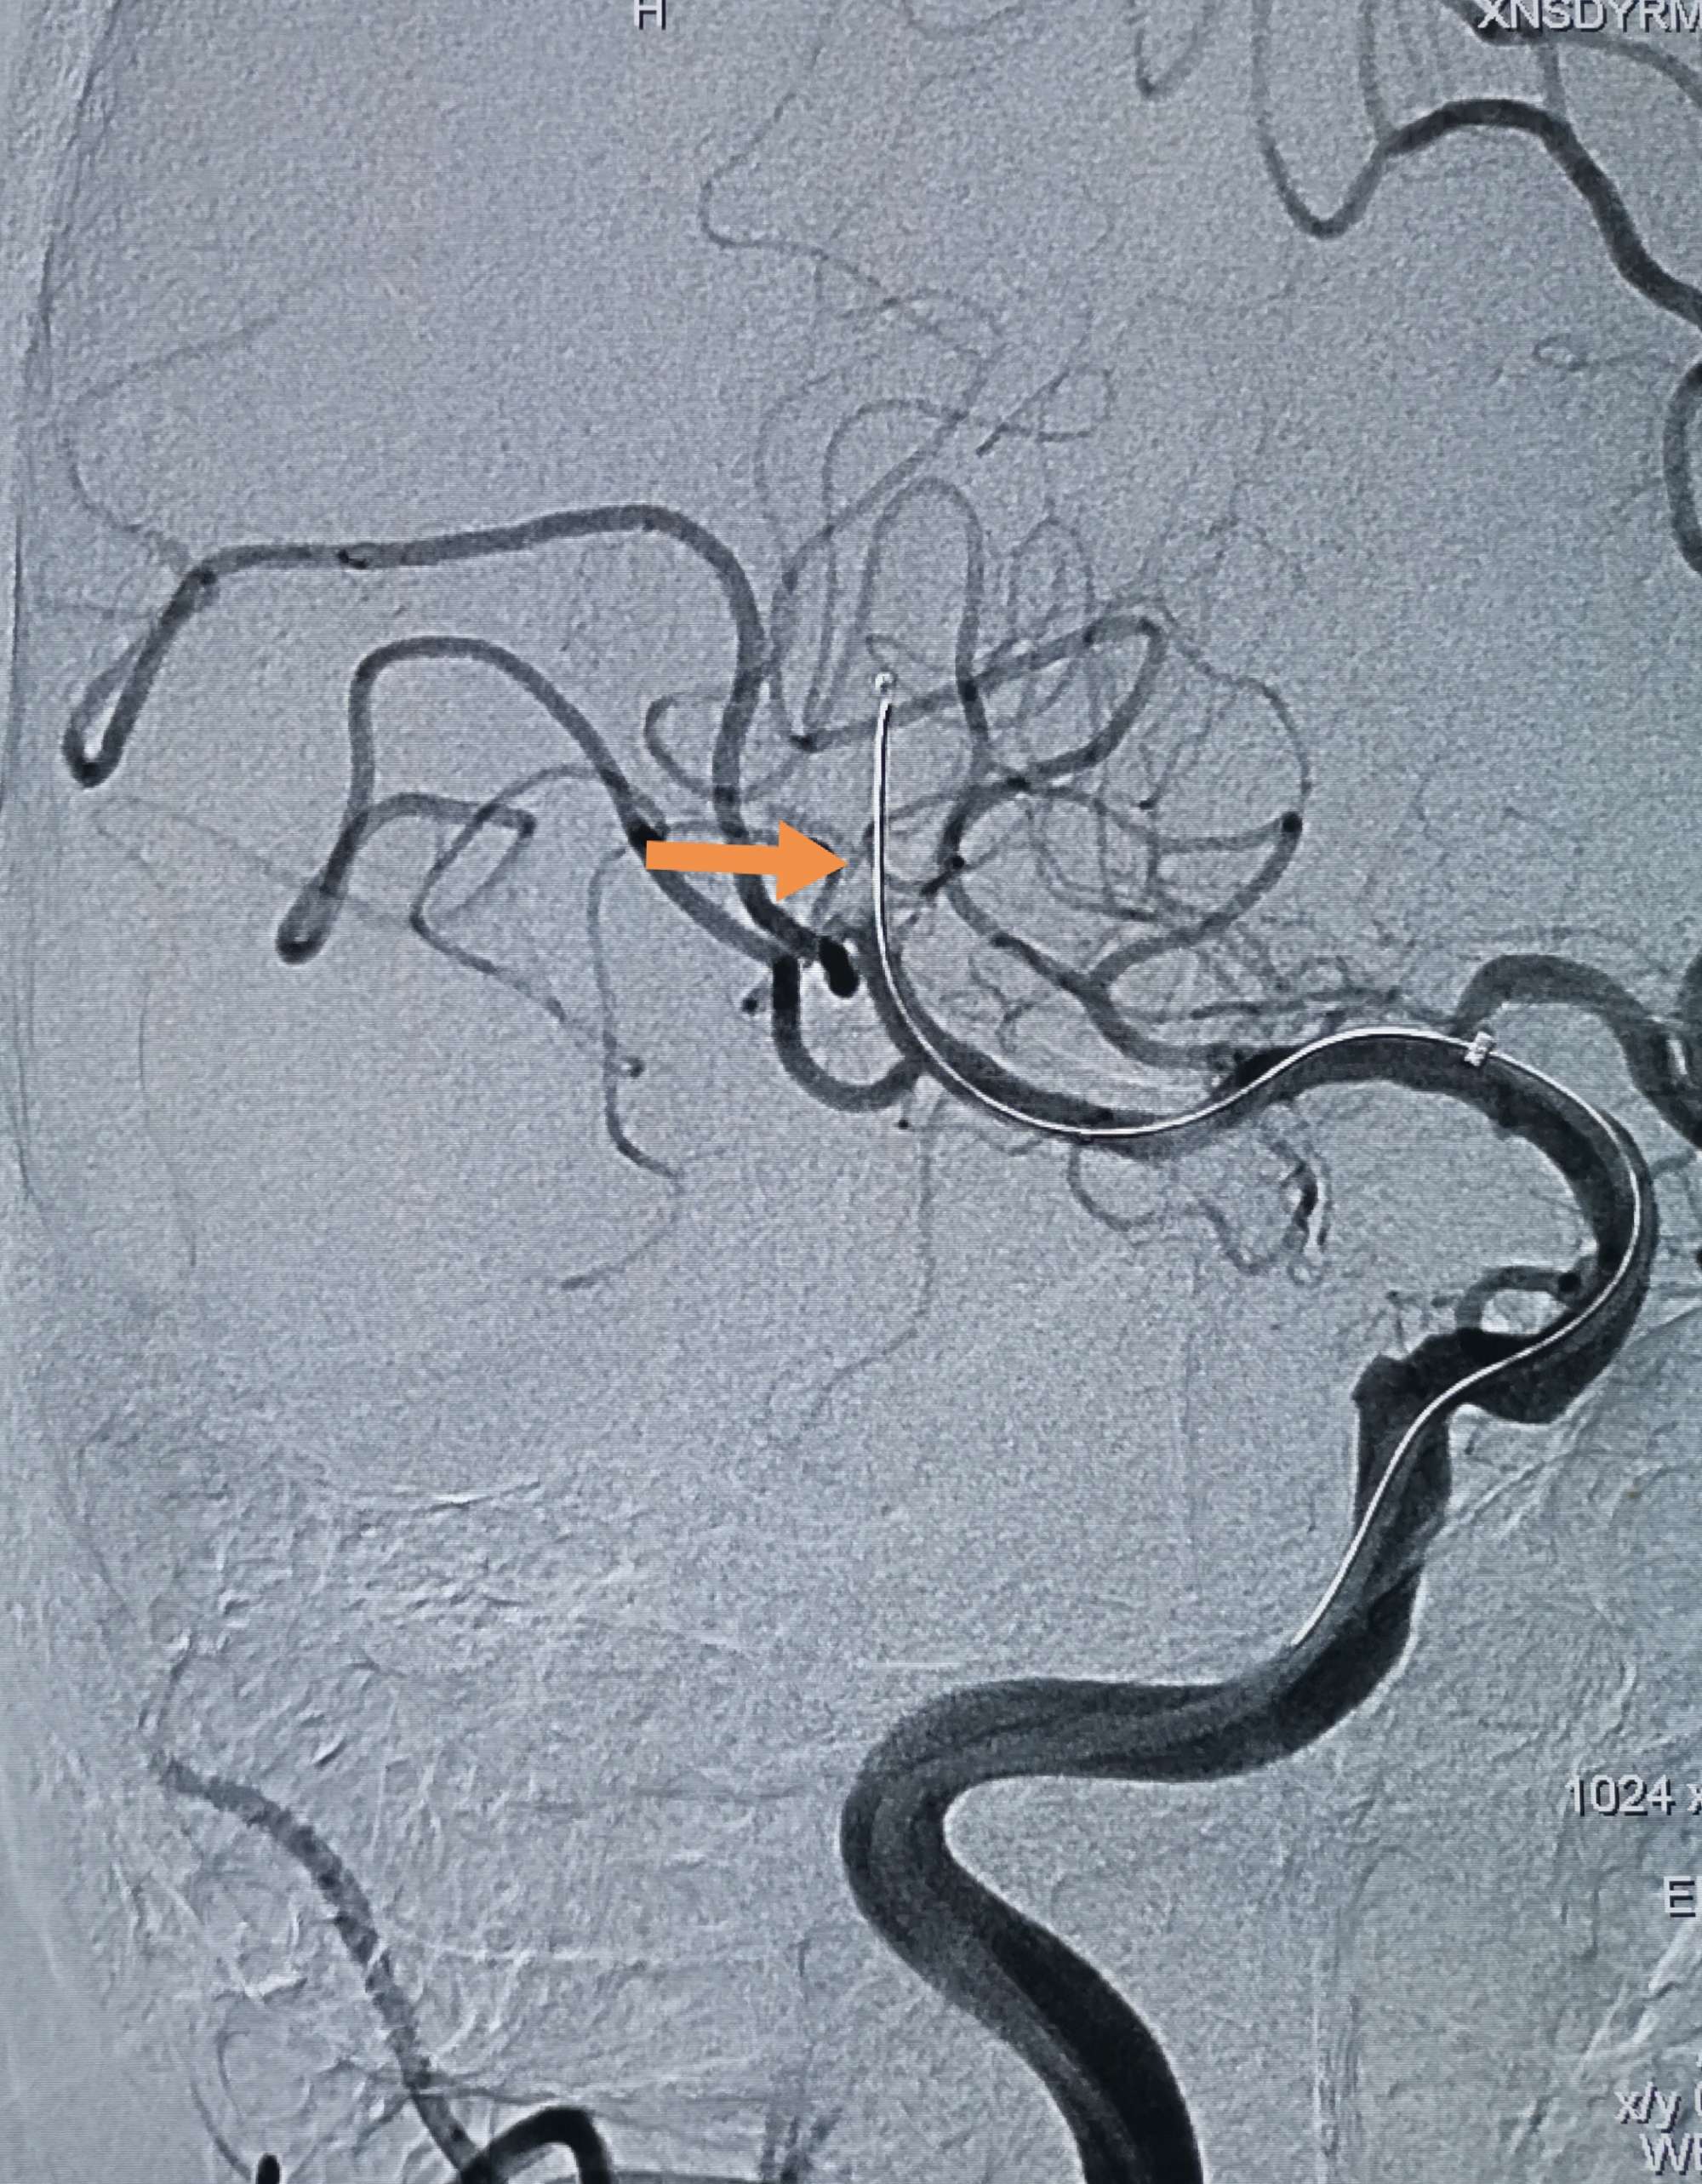

再次微导管内给予替罗非班0.05mg两次后造影,逃逸的血栓大部分被清理

正侧位造影,血栓大部分被清理,有少量残留,但远端血流通畅,此时,患者开始说话,言语清晰流利,左侧肢体肌力开始恢复,静脉泵入替罗非班,收台